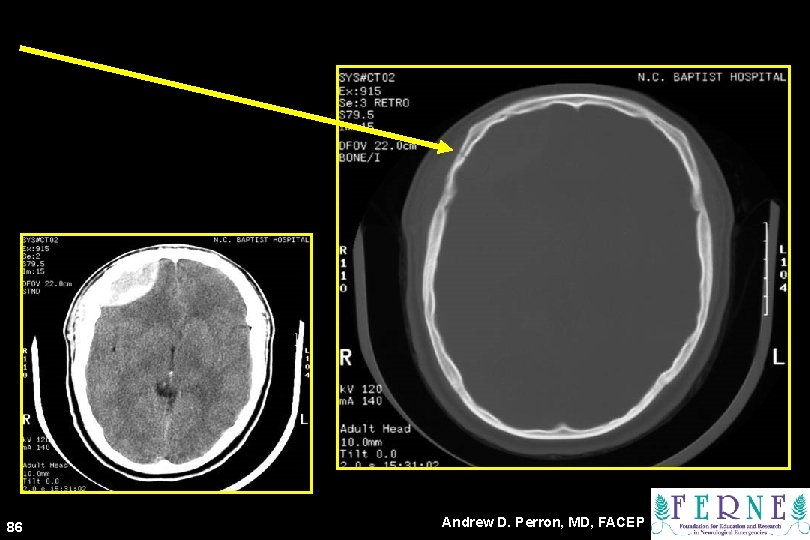

BONE 82 Andrew D. Perron, MD, FACEP

83 Andrew D. Perron, MD, FACEP

84 Andrew D. Perron, MD, FACEP

85 Andrew D. Perron, MD, FACEP

86 Andrew D. Perron, MD, FACEP